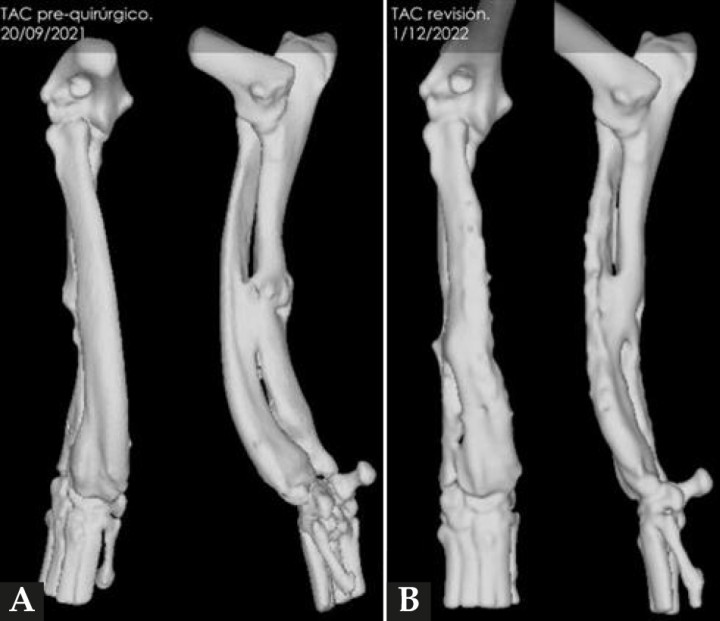

En cuanto a la evolución, resulta vital realizar radiografías de seguimiento postoperatorio con cierta periodicidad (Fig. 7). Esto nos permite tener un control adecuado del animal y actuar lo antes posible si se presentase algún contratiempo. En el caso que nos ocupa, además de las radiografías postoperatorias realizadas tras la cirugía correctiva y las efectuadas antes de retirar los implantes, se realizó una TC de revisión tras la extracción de los mismos (al año y dos meses de su colocación), observándose en 3D una buena remodelación y alineación de los huesos. Si comparamos estas imágenes de TC con las primeras, es decir, con las de la planificación quirúrgica antes de la corrección, se puede observar que la superposición de ambas TC muestra una alta precisión en lo que respecta al resultado obtenido (Fig. 8).

(A) Reconstrucción en 3D de los huesos del antebrazo afectado antes de realizar la ostectomía y colocar los implantes y (B) después de retirarlos.

Figura 8